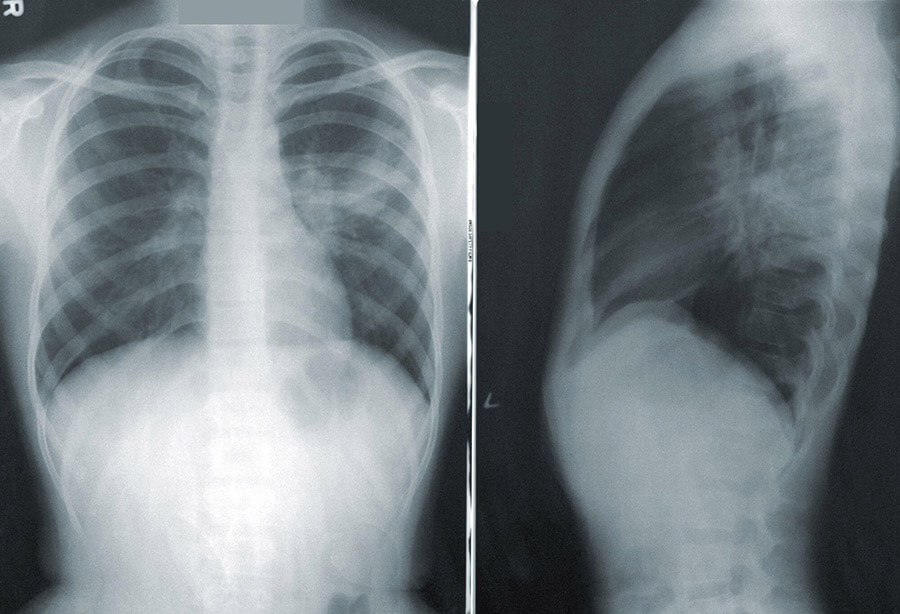

The doctor was exposed to the virus when the 38-year-old woman visited the clinic on March 12, the minister said. Five days later, she tested positive. That day, the doctor was also admitted in hospital.